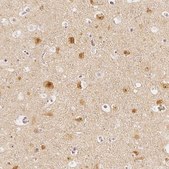

Rabbit polyclonal anti-ARHGAP26 antibody is used to tag Rho GTPase activating protein 26/ GTPase Regulator Associated with Focal Adhesion Kinase (GRAF) for detection and quantitation by immunocytochemical and immunohistochemical (IHC) techniques. It is used as a probe to determine the presence and roles of Rho GTPase activating protein 26/ GTPase Regulator Associated with Focal Adhesion Kinase (GRAF) in clathrin-independent endocytosis involving the CLIC/GEEC pathway.

• IHC tissue array of 44 normal human tissues and 20 of the most common cancer type tissues.